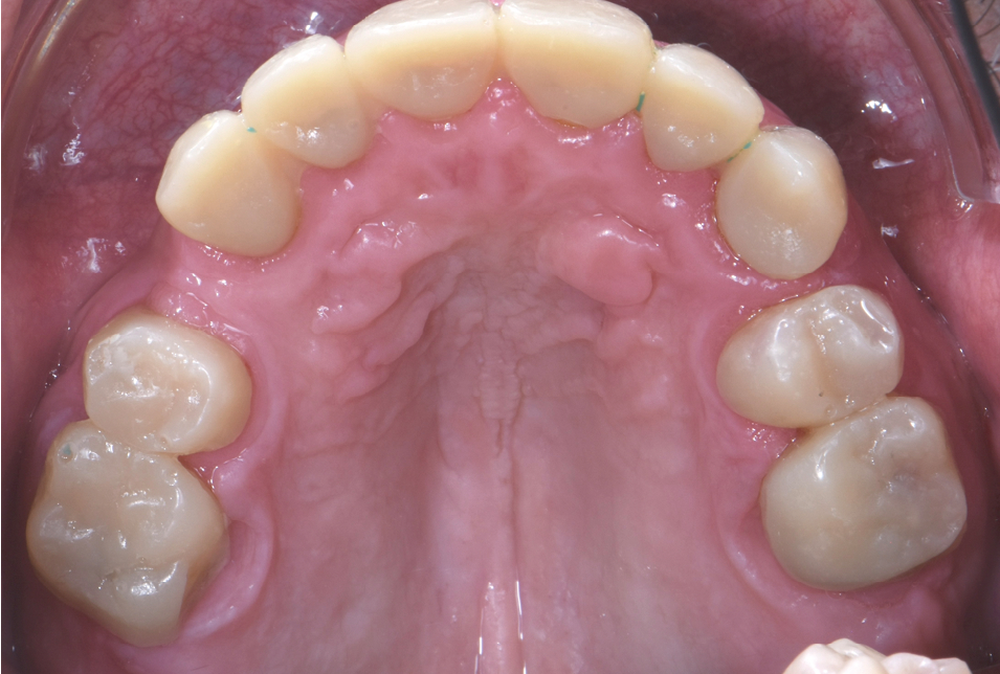

Au vu du contexte para-fonctionnel et de l’étendue de la perte tissulaire, des coiffes périphériques minimalement invasives ont été choisies afin de restaurer l’esthétique et la fonction. Actuellement, aucun consensus n’est fait sur le choix du matériau d’infrastructure à privilégier. Les matériaux hybrides usinables présentent des propriétés mécaniques, physiques et biologiques intéressantes en contexte d’usure sévère (e.g., module d’élasticité, résistance à la propagation de fêlures, facilité de réintervention). Une réhabilitation globale avec remontée de dimension verticale d’occlusion (DVO) par l’intermédiaire de coiffes composites renforcés en nano-céramiques est décrite.